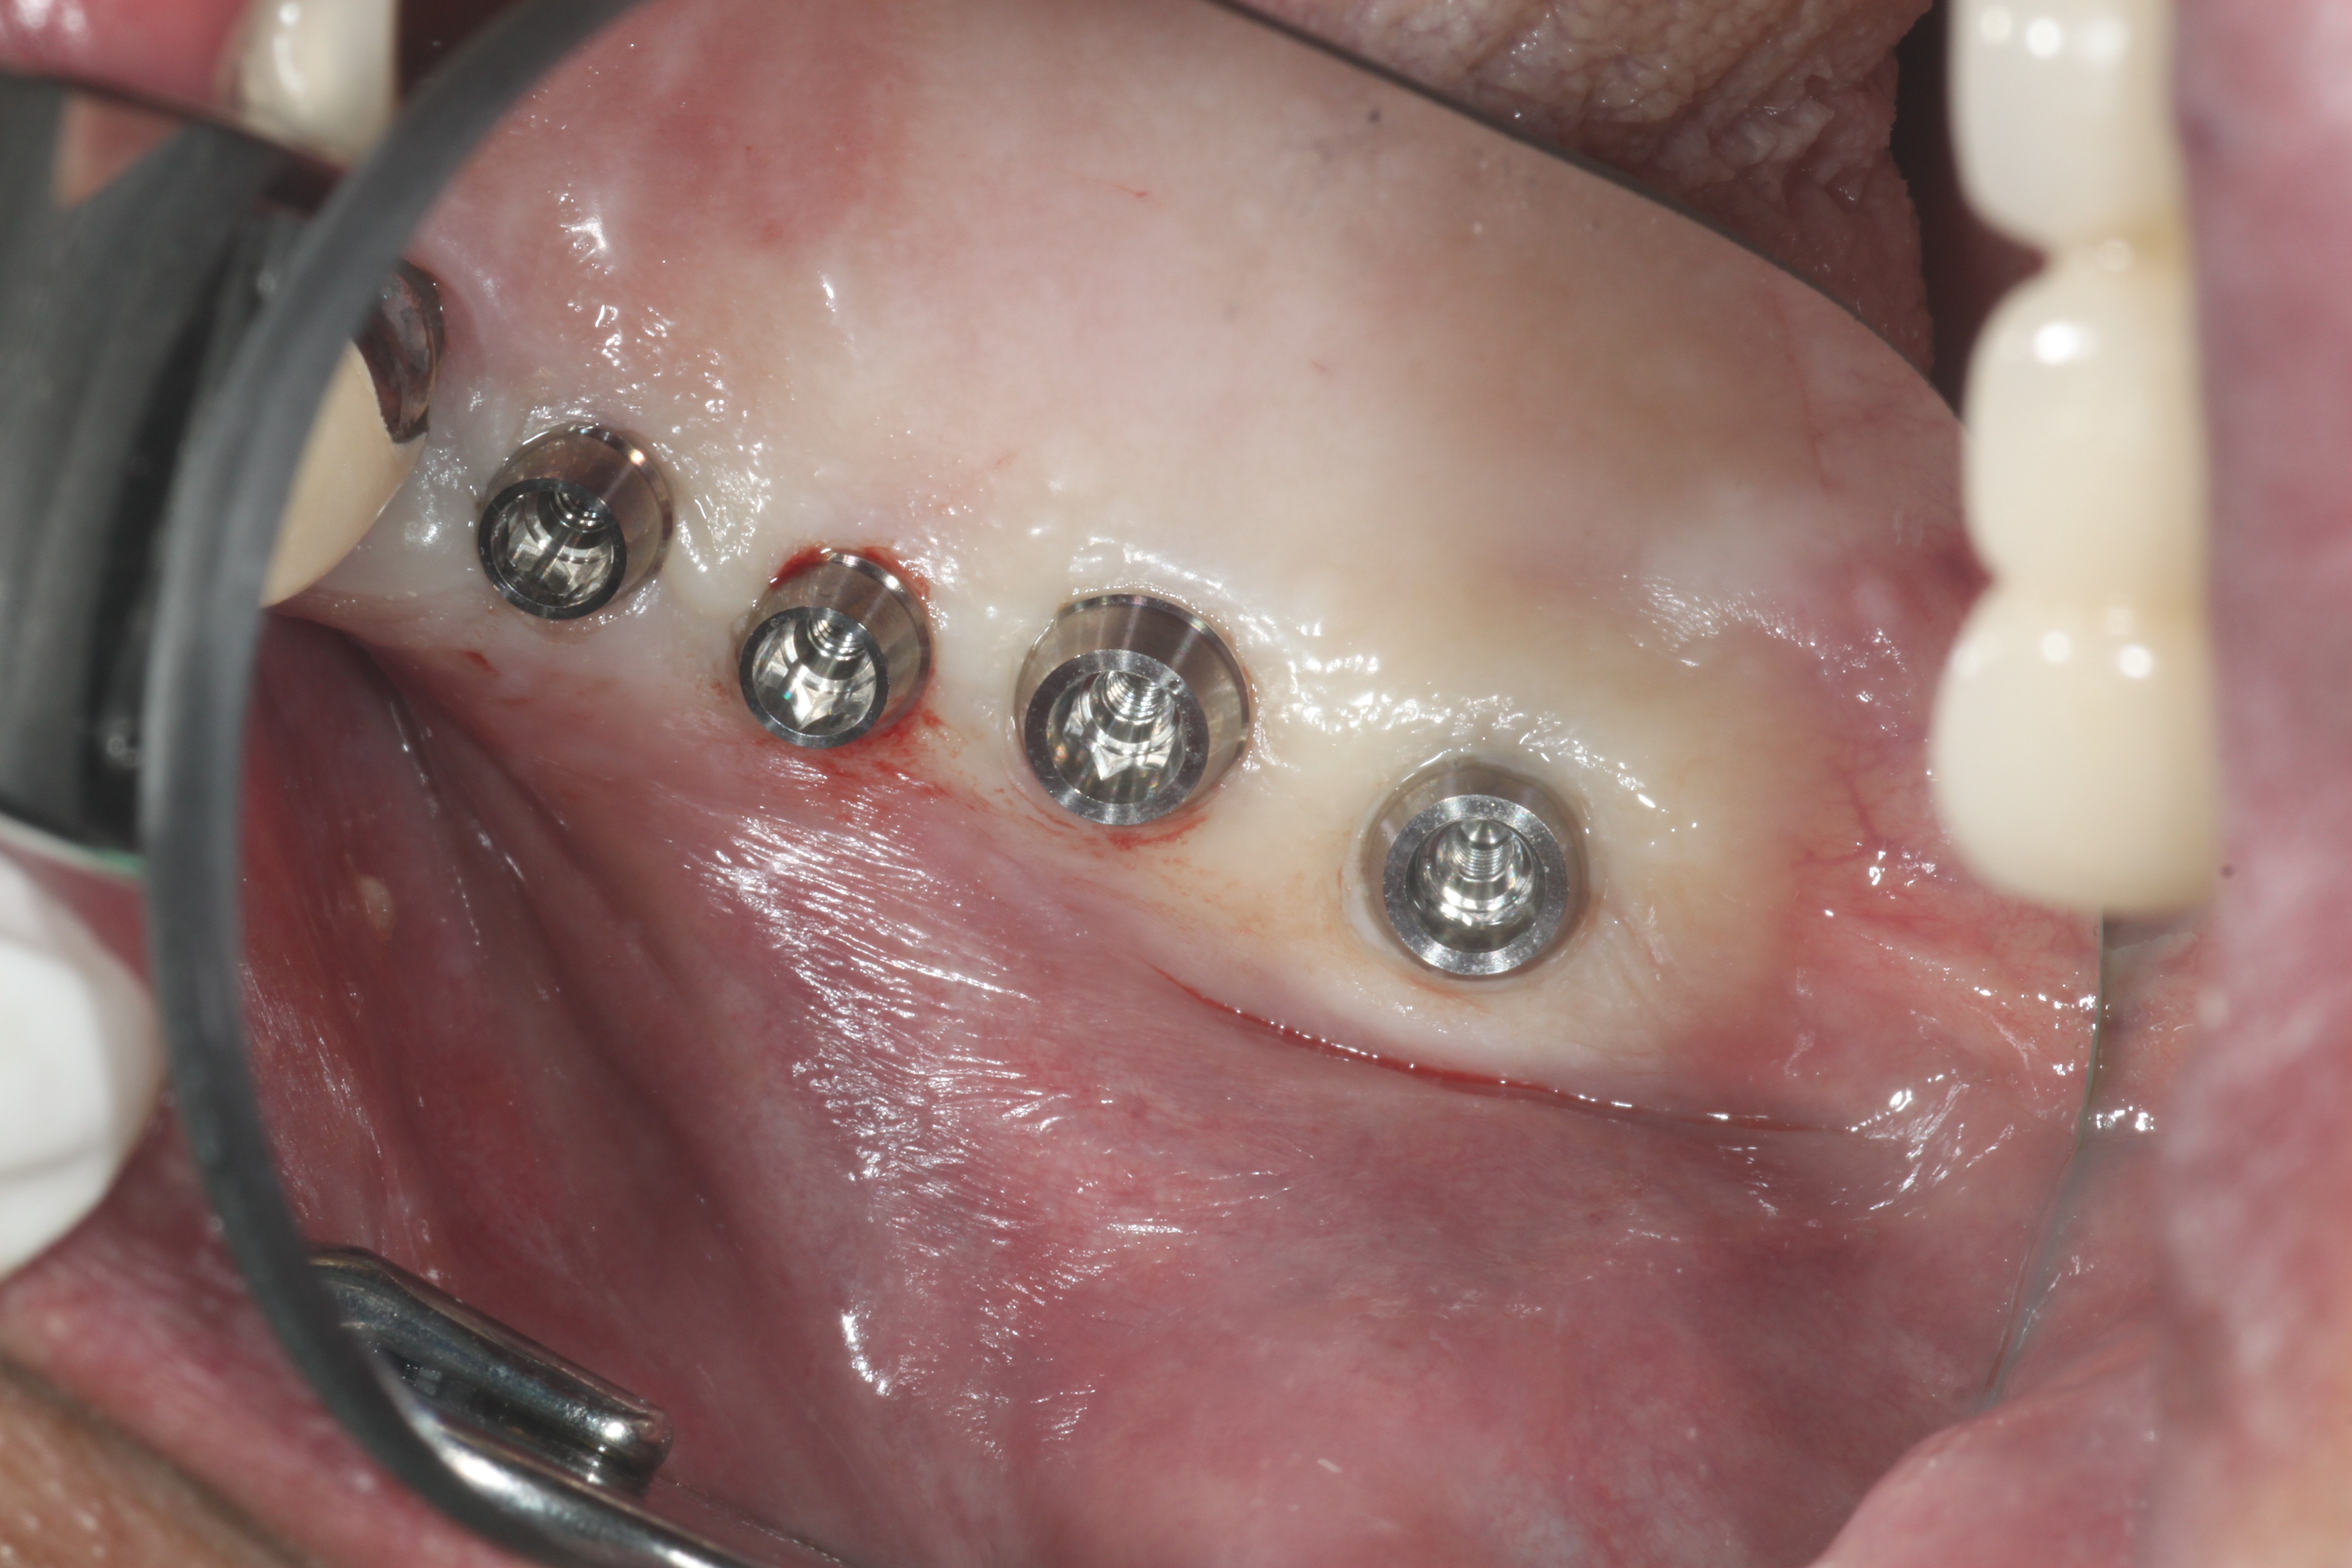

ÀÓÇöõÆ®¸¦ ½Ä¸³ÇÏ¿´À¾´Ï´Ù.

ȯÀÚºÐÀÌ ³Ê¹« ÆíÇϽôٰí ÇÕ´Ï´Ù.Çǰ¡ ¾È³ª°í¿ä.

½Ã¼ú½Ã ÀÕ¸öÀ» ¾à°£ Á¦°ÅÇϱ⿡ ±×¶§ ÇǸ¦ Á¶±Ý º¼¼ö ÀÖÁö¸¸ °ú´ÙÃâÇ÷À̳ª ½ÉÇÑ ¹ÝÀÀÀº ÀϾÁö ¾ÊÀ¾´Ï´Ù.

ÀÌ·± ÀÓÇöõÆ®´Â ÀÌÂ÷·Î ¼ö¼úÀ» ÇÏÁö ¾ÊÀ¾´Ï´Ù.»À¿¡ ºÙÀ¸¸é º¸Ã¶À» ¿Ã¸®±â°¡ ³Ê¹« ½±À¾´Ï´Ù.